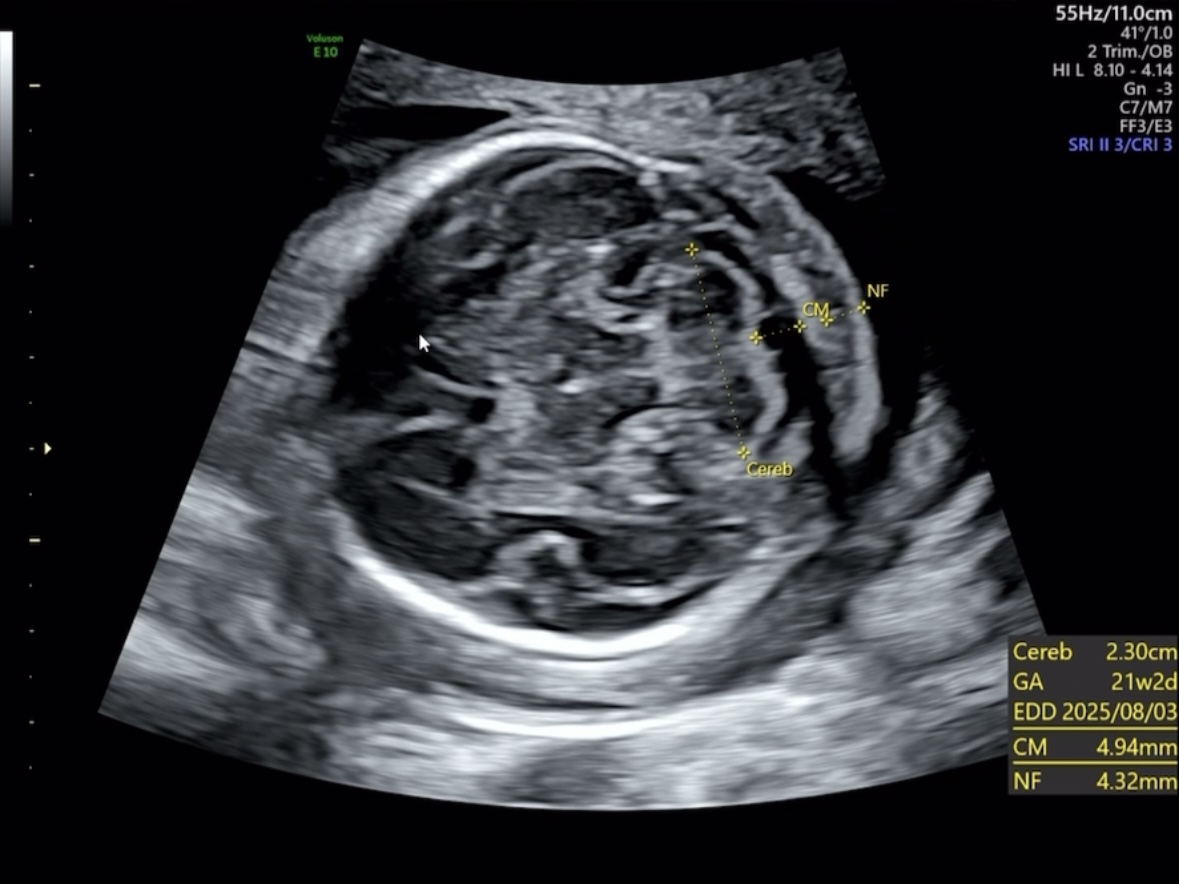

척추, 뇌

▒ 관련 초음파 용어

· Va(Ventricular Atrium): 대뇌 측뇌실(Atrium) 크기 측정(정상 범위: ≤10 mm)

· Vp: 대뇌 측뇌실의 뒤쪽(이상 소견 시 수두증 의심 가능)

· Cereb: 소뇌

· NF: 목덜미 두께(정상 범위: ≤6 mm, 21주 기준)

뇌도 정상적으로 발달했고 뇌실도 정상범위에 있었다.